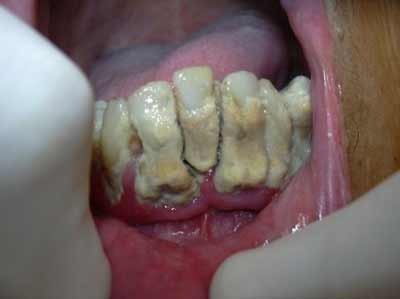

Lo studio dentistico del Dott. Peroni è situato a Flero in provincia di Brescia in via Vittorio Emanuele II, 49. Il Dott. Peroni è specializzato nella medicina chirurgica dentale ed odontoiatrica ed offre i seguenti servizi: Diagnostica, Igiene orale professionale, Restaurativa e Conservativa, Endodonzia, Chirurgia orale, Implantologia, Patologia orale, Ortodonzia, Posturologia, Analgesia Sedativa, Gnatologia, Pedodonzia e Protesi. Presso gli Studi Dentistici del Dottor Peroni ci prendiamo cura dei vostri denti e restauriamo il corretto stato delle vostre bocche. Per fissare un appuntamento con il Dottor Peroni o con i suoi collaboratori è possibile chiamare lo 030 2761577 o scrivere una mail a info@dentistaperoni.it.

Keywords ortognatodonzia, gnatologia, ortodonzia estetica, ortodonzia per bambini, pedodonzia, endodonzia, ortodonzia invisibile, ortodonzia chirurgica, trattamenti di igiene orale, patologia orale, igienisti dentali, sbiancamento denti, pronto soccorso dentistico, chirurgia dentistica, implantologia dentale, dentisti medici chirurghi ed odontoiatri, protesi fisse su denti naturali, analgesia sedativa, endodonzia conservativa, ortodonzia posturale.